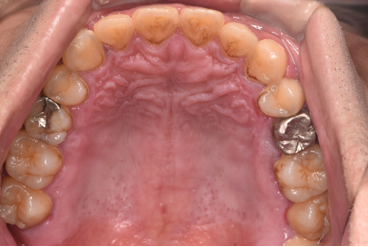

治療後

| 行ったご提案・治療内容 | 初診時に撮影したレントゲン、口腔内写真、歯周病検査の結果を用いて、歯周病治療の必要性をお伝えしました。 初診時は歯ブラシの使い方などセルフケアの方法をご説明し、その後に歯肉縁上歯石(歯肉より上に付く黄色または乳白色の歯石)を除去しました。 歯肉の炎症がある程度落ち着いた後日、再評価を行い、歯周治療へ移行しました。 |

| 術後の経過・現在の様子 | 経過は良好です。 |